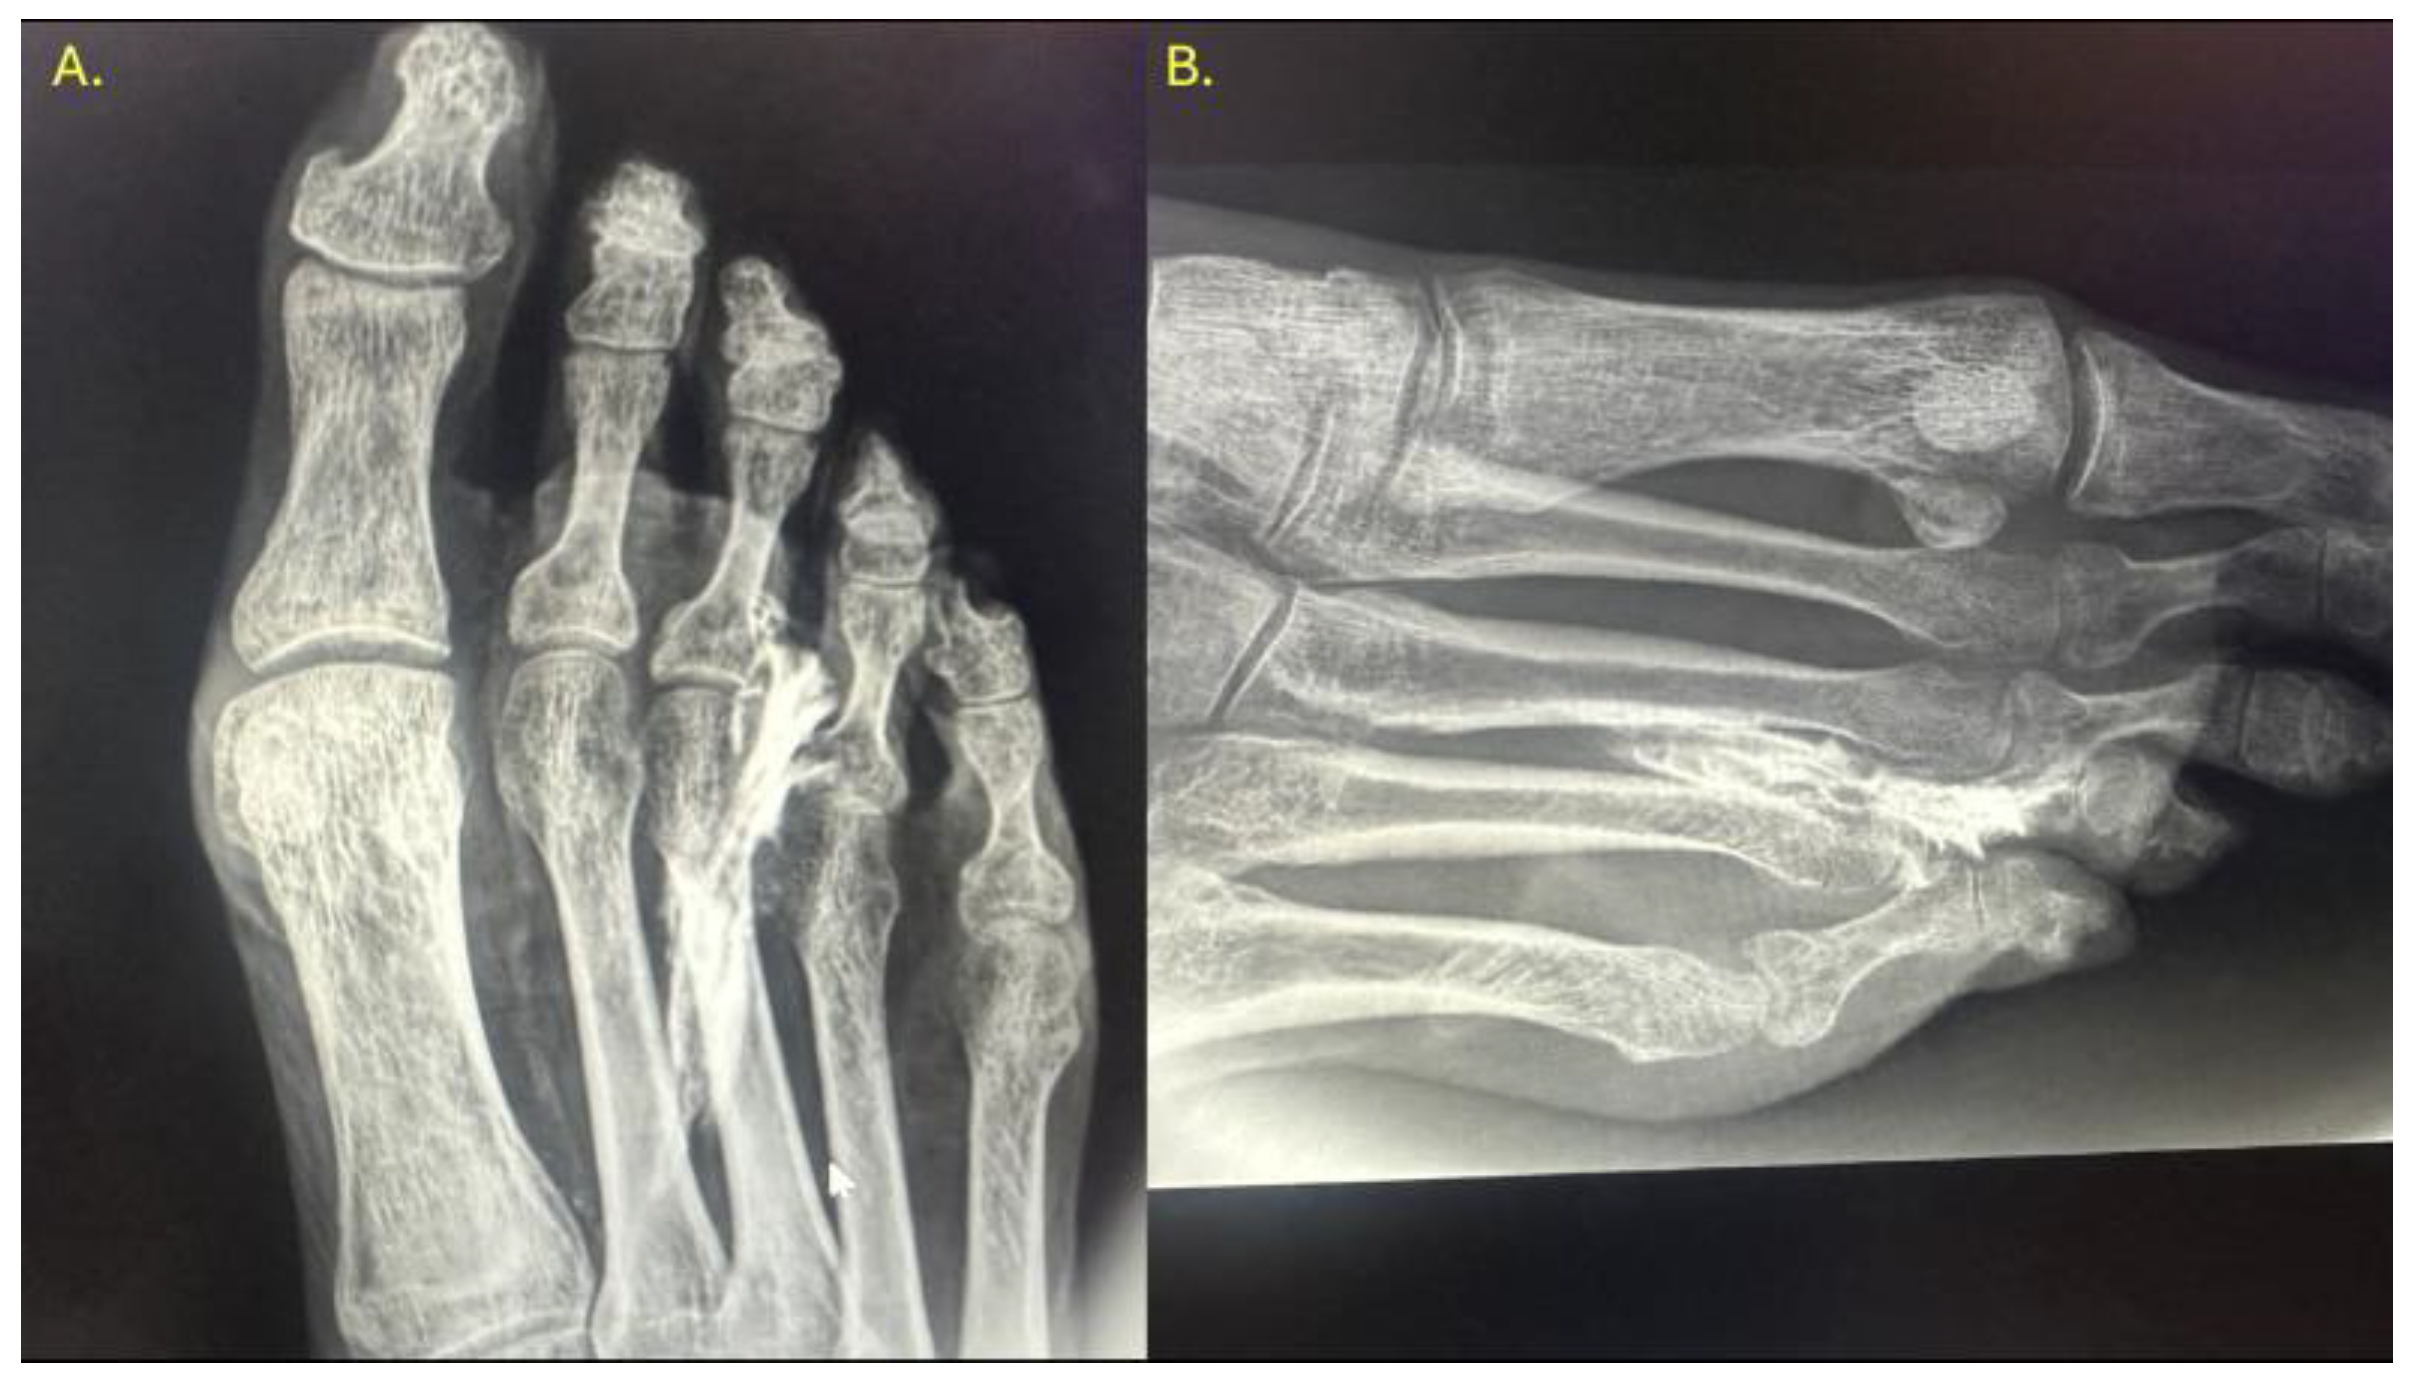

In all specimens, IM space infiltration resulted in diffuse, uncontained dispersion with irregular expansion and poorly defined borders (Figure 4). The contrast extended both proximally and laterally into adjacent soft tissue planes, following fascial paths with no clear anatomical containment. Additionally, a tendency for contrast migration toward the plantar region was observed, following the trajectory of the common plantar digital nerve. The mobility and superficial location of this nerve within the IM space appear to facilitate the lack of containment. This pattern confirms that the IM space functions as an anatomically open cavity with higher permeability to infiltrated fluid.

Figure 4. Ultrasound-guided injection of 0.5 cc of radiopaque contrast targeting the third common plantar digital nerve. The injection was performed in long axis, with a distal-to-proximal trajectory parallel to the nerve. (A) Dorsoplantar projection of the right forefoot. (B) Oblique projection of the same injection, allowing for better visualization of the contrast tracking along the interdigital space.